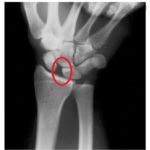

Scapholunate dissociation

SCAPHOLUNATE DISSOCIATION Rajesh Purushothaman, MS, Associate Professor, Govt.Medical College, Kozhikode, India According to Dobyns, carpal instability is “a carpal injury in which loss of normal alignment of the carpus occur early or late”. . Scapholunate dissociation (SLD) is the most common type of carpal instability. It is the most common instability pattern because the intercarpal […]